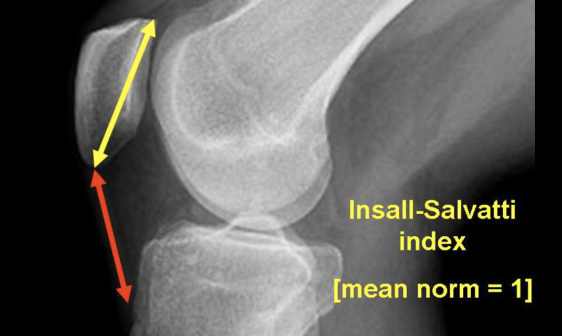

Hauteur rotulienne

- Patella Alta si >1.3-1.5